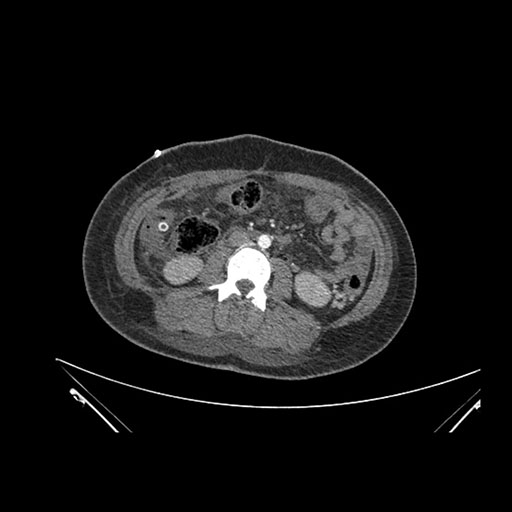

Imaging Analysis

Look through the patient's CT scan to identify any areas of concern for the necessary procedure.

Axial Venous